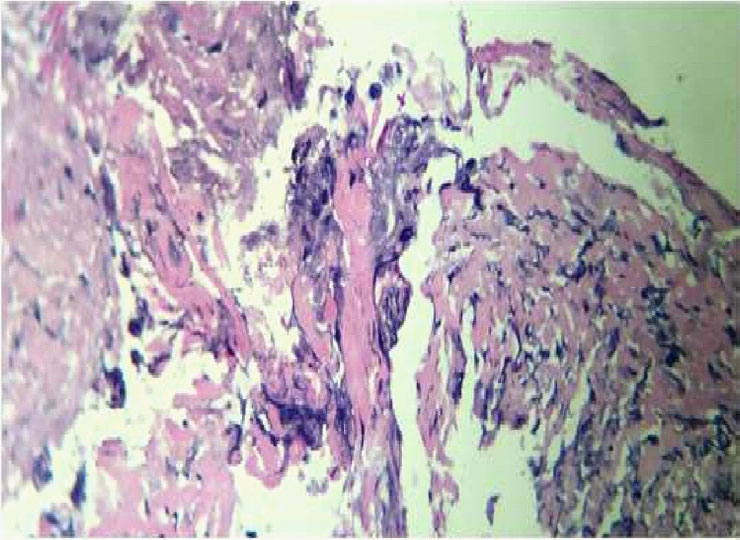

49 yr old gentleman, who underwent Mini gastric bypass for morbid obesity in 2013, presented with chief complaints of pain abdomen since 3 days, more in the epigastrium, radiating to back, associated with breathlessness and left sided chest pain. His BMI was 44.5. The patient was vitally stable and afebrile. His abdomen was soft, non-distended, diffuse tenderness was present and there was no organomegaly. Computed Tomography (CT) abdomen revealed pneumoperitoneum with small volume collection in perisplenic region. Efferent jejunal loop appeared mildly edematous with few inter bowel foci of trapped air (Figure 1). Hence patient was taken up for diagnostic laparoscopy.

Figure 1:CT abdomen

Figure 4:Periodic Acid Schiff's (PAS ) stain showing Candidal spore and Pseudohyphae.

Figure 5:Gomori methenamine silver stain